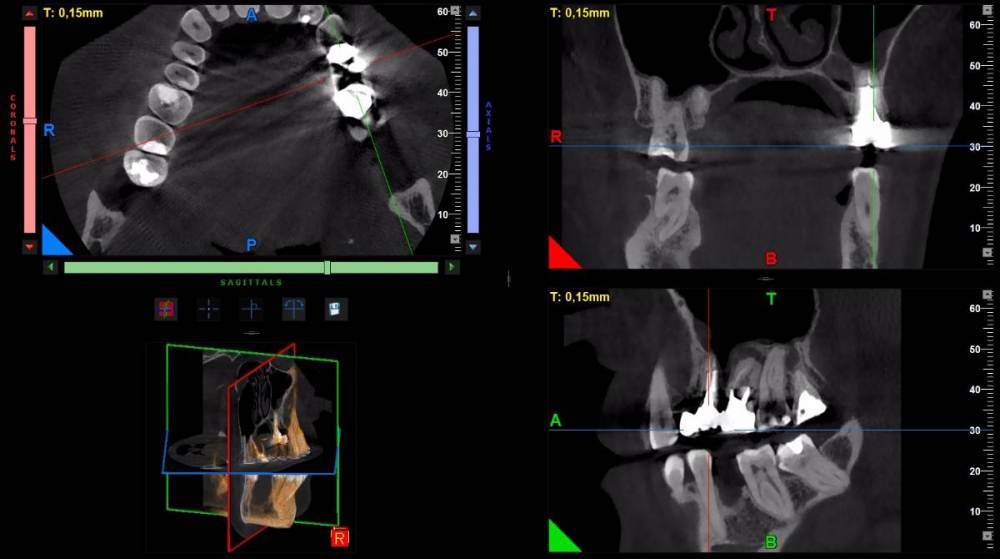

DeLaMer Опубликовано 11 августа, 2021 Поделиться Опубликовано 11 августа, 2021 (изменено) Добрый день уважаемым докторам-участникам форума. Хотелось бы, по возможности, получить экспертное мнение по поводу моей проблемы. На верхней челюсти есть мост, объединяющий 6й, 5й и отсутствующий 4 зубы (если я правильно понимаю нумерацию, это должны быть 24, 25, 26). В начале июня на десне открылся свищ с гноем (абсцесс, но, видимо, не острый, кроме периодического надувания гнойного шарика ничего больше не происходило). По этом поводу мой лечащий врач поднял КТ, которое было сделано осенью до того по другому поводу и обнаружила воспаление одного из корней 6-го зуба. При этом она высказала соображение, что может быть здесь поможет резекция верхушки того самого корня. Один из хирургов, с которым я консультировалась по этому поводу, сказал, что на его взгляд резекция возможна. Другой - что воспаление проявляется не только на одном корне, а на двух и по его мнению сделать тут ничего нельзя, только распиливать коронку и удалять 6й зуб. Я была бы крайне благодарна, если бы уважаемые специалисты высказали свое мнение по этому поводу, потому что при равноценных двух противоположных мнениях мне даже не понятно с чего начинать. Прикрепляю ссылку на файл КТ на своем дропбоксе. Огромное спасибо за помощь https://www.dropbox.com/s/fkv8cvqqq6grgpe/Sergeeva A..zip?dl=0 Изменено 11 августа, 2021 пользователем DeLaMer Ссылка на комментарий

Irouil Опубликовано 12 августа, 2021 Поделиться Опубликовано 12 августа, 2021 На мой взгляд тут резекция верхушки корня не поможет так как верхушка корня - далеко не единственная проблема этого зуба Ссылка на комментарий

Irouil Опубликовано 12 августа, 2021 Поделиться Опубликовано 12 августа, 2021 По представленным средам создаётся впечатление, что у зуба фактически разрушено соединение между корнями. Риски того, что он под нагрузкой раскроется в любой момент, достаточно высоки Ссылка на комментарий

АнтонТЛТ Опубликовано 13 августа, 2021 Поделиться Опубликовано 13 августа, 2021 (изменено) Там всё ок с фуркацией и вкладка коротконогая. Просто на КТ очень много артефактов. Изменено 13 августа, 2021 пользователем АнтонТЛТ Ссылка на комментарий